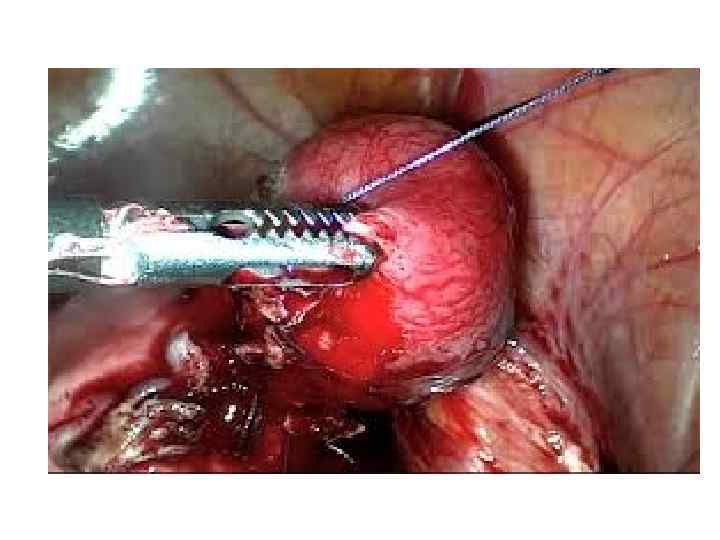

В качестве методов хирургического лечения перфорации язвы желудка и двенадцатиперстной кишки применяют: 1) ушивание язвы; 2) иссечение язвы + дренирующая желудок операция; 3) резекцию желудка; 4) ваготомию с иссечением язвы и дрени рующей желудок операциейили ушиванием язвы; 5) ваготомию с экономной резекцией желудка.

1) Предварительная (временная) остановка наружного кровотечения: 2) Хирургические вмешательства по поводу заболеваний внутренних органов, осложнившихся кровотечением, экстренные хирургические операции по поводу травматических повреждений кровеносных сосудов имеют целью ликвидировать патологический очаг или восстановить магистральный кровоток. Все эти мероприятия могут быть определены как обеспечение окончательной остановки кровотечения. 3) Однако радикальные хирургические вмешательства достигают полного и быстрого эффекта только при условии борьбы с острой постгеморрагической анемией. Поэтому эффективное лечение острой анемии и профилактика последствий кровопотери определяют исходы лечения кровотечений любой этиологии.